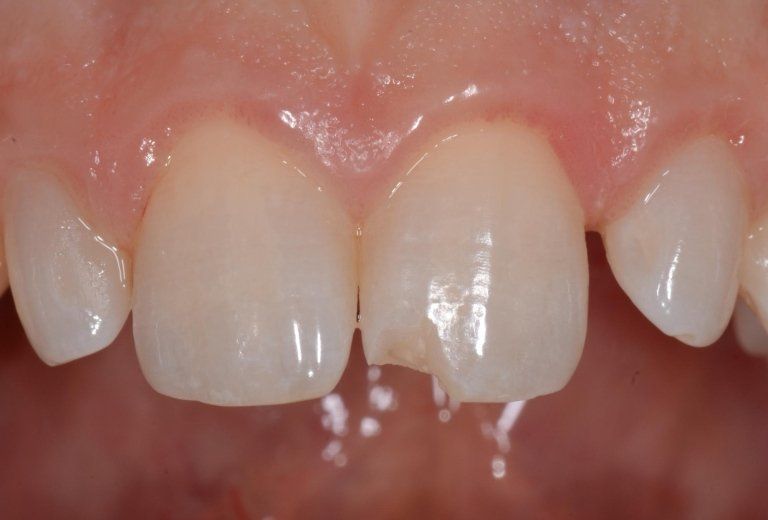

I denti da latte traumatizzati più spesso vanno incontro a necrosi con conseguente cambiamento di colore, divenendo grigiastri, segno della morte delle cellule della polpa dentaria. In altre occasioni, il dente può fratturarsi in maniera più o meno ampia: se il frammento viene ritrovato, potrà essere re-incollato in maniera invisibile, oppure verrà ricostruito con i materiali compositi.